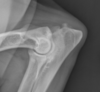

What is shown in this radiograph?

columnar periosteal reaction